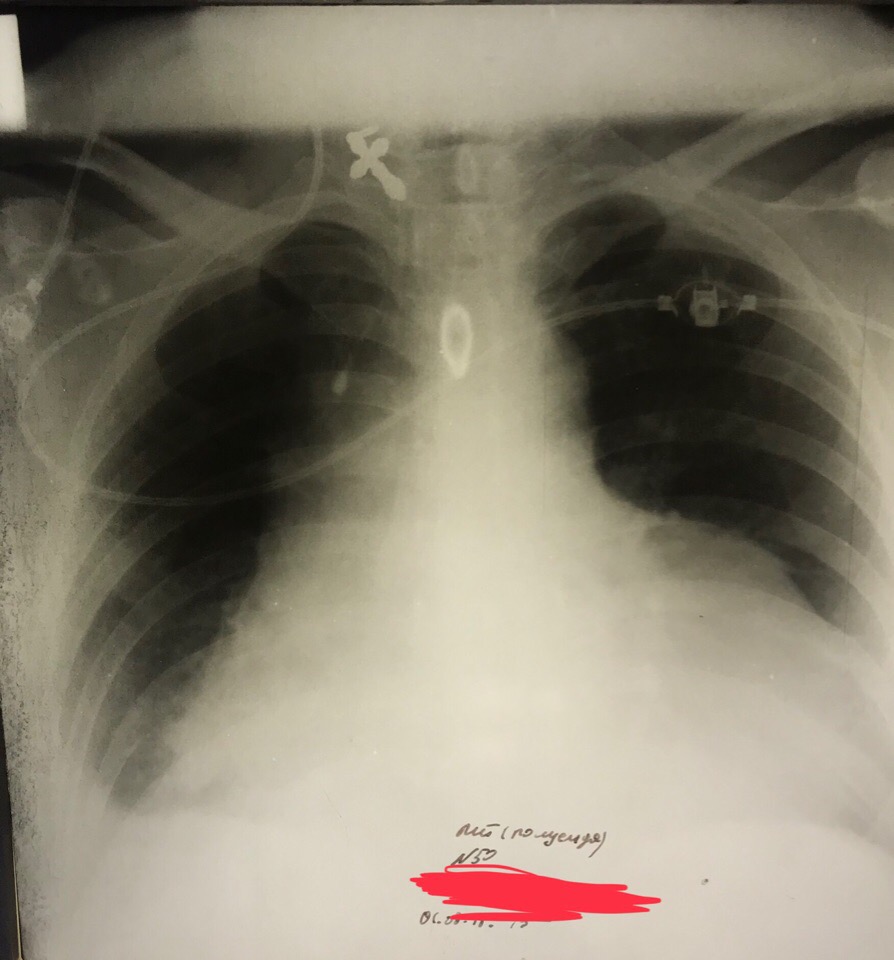

Заголовок сообщения: Эксудативный перикардит

F5VlO9t1UOQ.jpg

F5VlO9t1UOQ.jpg [ 120.41 KiB | Просмотров: 12426 ]